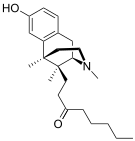

Others

- 1-Nitroaknadinine * 14-episinomenine

- 5,6-Dihydronorsalutaridine

- 6-Keto Nalbuphine

- Aknadinine

- Butorphanol

- Cephakicine

- Cephasamine

- Cyprodime

- Drotebanol

- Fenfangjine G

- Ketorfanol

- Nalbuphine

- Nalbuphone

- Tannagine

Structures

| Other Morphinans | ||||

|---|---|---|---|---|

1-Nitroaknadinine 1-Nitroaknadinine |

14-episinomenine 14-episinomenine |

5,6-Dihydronorsalutaridine 5,6-Dihydronorsalutaridine |

6-Keto Nalbuphine 6-Keto Nalbuphine |

Aknadinine Aknadinine |

Butorphanol Butorphanol |

Cephakicine Cephakicine |

Cephasamine Cephasamine |

Cyprodime Cyprodime |

Drotebanol Drotebanol |

Fenfangjine G Fenfangjine G |

Nalbuphine Nalbuphine |

Sinococuline Sinococuline |

Sinomenine Sinomenine |

Tannagine Tannagine |